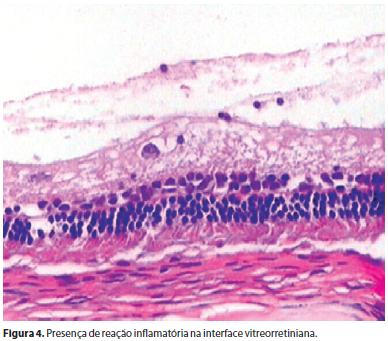

Não foram encontrados descolamento e edema de retina e nem percebidas alterações histológicas na retina sensorial, epitélio pigmentar e coroide de todos os olhos estudados. Não se constataram sinais de atrofia e edema tanto nas células como na espessura das camadas retinianas e da coroide (Figura 2). Uma pequena alteração encontrada em quatro e seis olhos submetidos a duas e três aplicações de infliximabe respectivamente foi a presença, no vítreo, de raros linfócitos e eosinófilos, sem comprometimento retiniano e sem significado clínico (Figura 3). Uma única alteração clinicamente significativa encontrada nos dois olhos de um único coelho que foi submetido a duas e três aplicações de infliximabe, foi uma reação infamatória com presença de fibrina no vítreo posterior, sem alterações na camada de células ganglionares e no restante do vítreo (Figura 4).

Em dois olhos de um mesmo coelho, submetido a duas e três aplicações de infliximabe notou-se reação inflamatória bem mais acentuada, com aparecimento de material fibrinoide no vítreo posterior, sem comprometimento da retina sensorial, que pode ou não estar relacionado ao uso do medicamento, mas sem valor estatístico. Possíveis razões para a resposta inflamatória à injeção intravítrea de infliximabe incluem reações ao anticorpo monoclonal, a proteínas desconhecidas ou a contaminações presentes com o uso da droga.

Após avaliação dos exames clínico-oftalmológicos, anatomopatológicos e eletrorretinográficos pode-se afirmar que duas e três injeções intravítreas de infliximabe na dosagem de 2 mg, em intervalos mensais, não provocam alterações tóxicas nas retinas de coelhos. A única alteração encontrada foi a presença de raros linfócitos e eosinófilos clinicamente insignificantes no vítreo, decorrentes ou de uma pequena reação inflamatória ou, mais provavelmente a micro-hemorragias em reabsorção causadas pelo trauma cirúrgico das injeções intravítreas. Não houve comprometimento na estrutura histológica das camadas sensoriais retiniana e do nervo óptico. Em um único coelho submetido a duas e três aplicações de infliximabe, foi encontrada uma reação fibrinoide, sem comprometimento das camadas da retina sensorial e sem valor estatístico significante. Essa alteração só foi detectada ao exame anatomopatológico, não tendo sido visualizada ao exame oftalmoscópico.